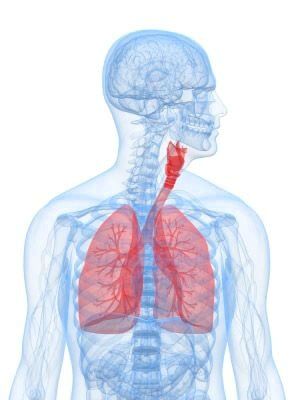

Загальні положення емфіземи легенів

Назва походить від грецького «надувати». Лікарі називають емфіземою таке захворювання легенів, коли розширені повітряні простори у дистальних бронхіол, з виникненням деструкції альвеолярних стінок. Іншими словами, в легенях відбувається підвищене газоутворення в альвеолярної тканини, причому в легких накопичується не киснем, а вуглекислий газ і інші домішки, які порушують кровотік в органах дихання і призводять до деструкції. А це, в свою чергу, негативно впливає на серце. Підвищується тиск всередині легких, через це стискаються внутрішні артерії, що викликає навантаження на серцевий м'яз і виникає хвороба - хронічне легеневе серце.

У хворих емфіземою повітря в легенях накопичується у великій кількості і ніяк не бере участі в процесі дихання. Через це тканина органу перерозтягується і стає нездатною працювати як раніше. Як наслідок скорочувальна здатність легких втрачається, і людина отримує кисневе голодування. Сполучна тканина розростається в легенях і бронхах, заміщаючи повітряні ділянки легких, і виникає бронхоспазм. Через цих змін виникають повітряні мішки в легких різноманітного розміру.